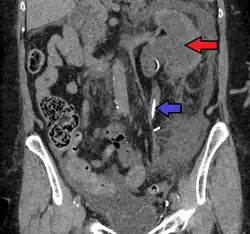

CT scan of bilateral hydronephrosis due to a bladder cancer CT scan of bilateral hydronephrosis due to a bladder cancer